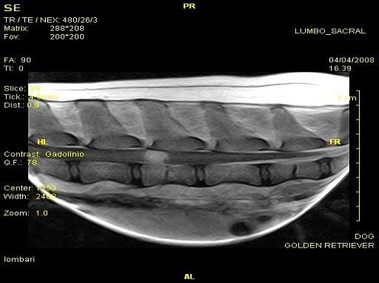

В настоящее время МРТ является наиболее предпочтительным методом визуализации любых мягких тканей, особенно для визуализации травм и патологий центральной нервной системы и суставов. Особенности Vet-MR позволяют использовать данный метод визуализации также в сфере ветеринарии.

Vet-MR специально разработана для визуализации небольших животных и является результатом внимания к деталям при разработке магнита, катушки и электронных компонентов, обеспечивая высокое качество экономически эффективной и простой в использовании МРТ в сфере ветеринарии.

- Высокое качество изображения